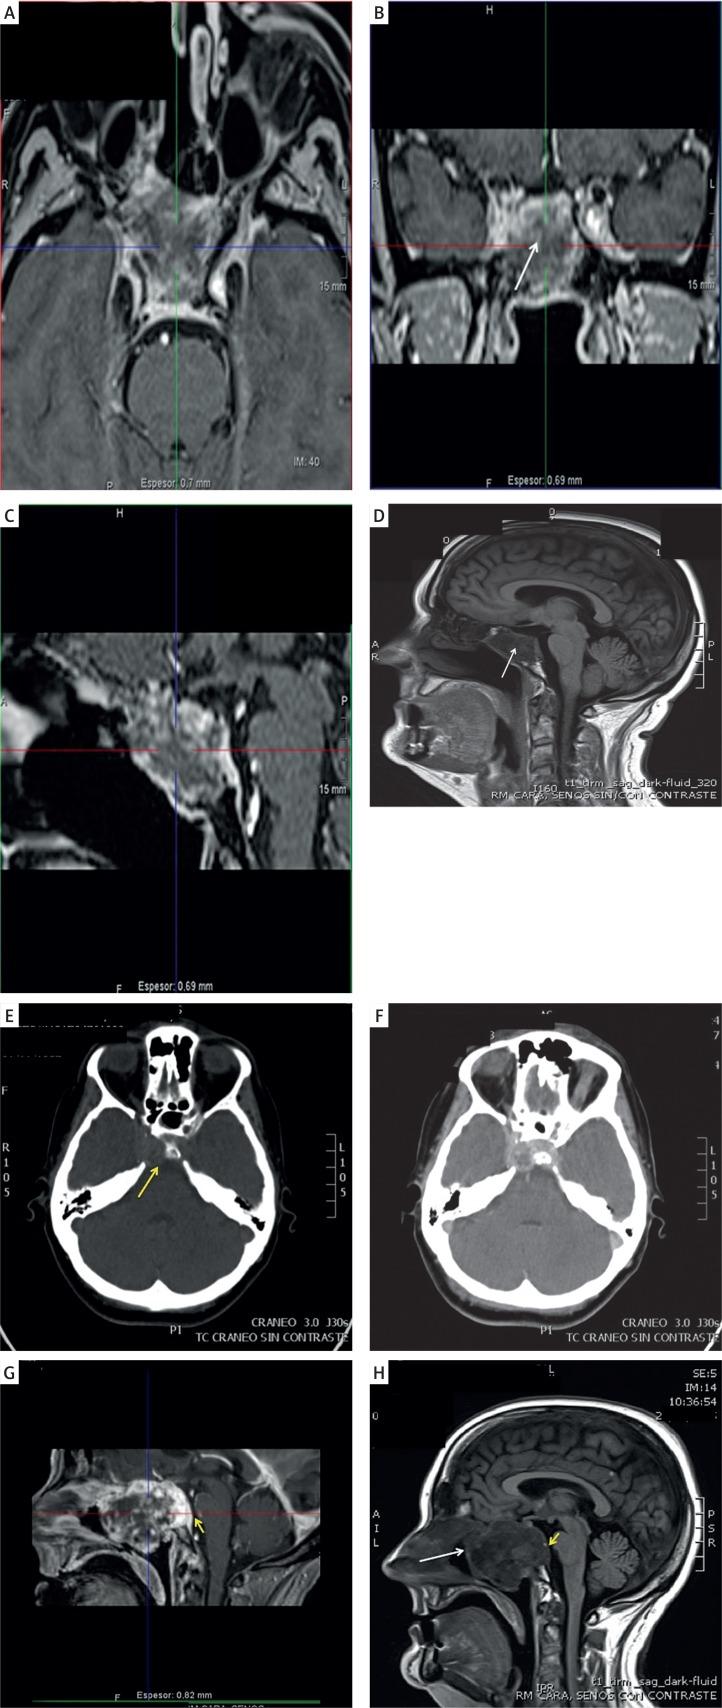

Epithelioid haemangioendothelioma (EHE) is a rare low-grade vascular neoplasm that is composed of mostly epithelioid cells. EHE may arise as a solitary tumour or in the form of multiple body lesions, and commonly occurs in soft tissues, liver, pleura, lung, peritoneum, lymph nodes, breast, and many other sites. EHE in the cranionasal region is extremely rare. There are very few reports of cases of skull-base EHE. We discuss an extremely rare presentation of an aggressive EHE that originated from the sellar region. Based on literature review, our patient is the first reported case of a giant solitary EHE with prepontine cistern invasion and abducens nerve encroachment mimicking a chondrosarcoma. We treated this rare tumour by near subtotal surgical excision with subsequent radiotherapy, considering that complete tumour resection with free margins in both cavernous sinus and clival region avoiding neural and vascular structure encroachment becomes technically difficult.

上皮样血管内皮瘤(EHE)是一种罕见的低级别血管肿瘤,主要由上皮样细胞组成。EHE可表现为孤立性肿瘤或多发性全身病变,常见于软组织、肝脏、胸膜、肺、腹膜、淋巴结、乳腺及许多其他部位。颅鼻区域的EHE极为罕见。关于颅底EHE的病例报道非常少。我们讨论了一例起源于鞍区的侵袭性EHE的极其罕见的病例。基于文献回顾,我们的患者是首例报道的巨大孤立性EHE,侵犯脑桥前池并压迫展神经,酷似软骨肉瘤。考虑到在海绵窦和斜坡区域实现肿瘤完整切除且切缘阴性,同时避免侵犯神经和血管结构在技术上具有难度,我们对这例罕见肿瘤进行了近全手术切除并随后进行放疗。